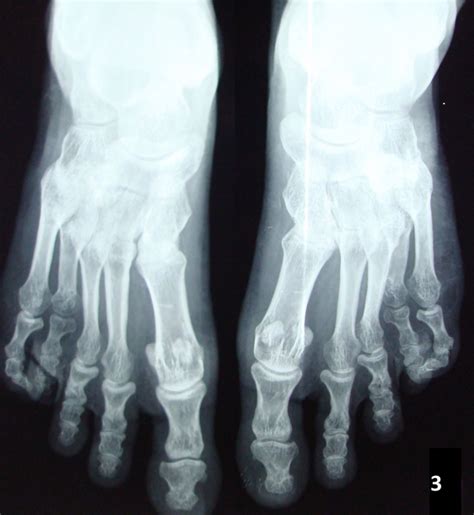

• Brachydactyly: Shortening of the bones in the hands and feet, particularly the fourth and fifth metacarpals and metatarsals.

• Clinical Evaluation: A thorough physical examination to assess the characteristic features of AHO, such as short stature, obesity, and brachydactyly.

• Orthopedic Interventions: Surgical procedures may be required to correct skeletal abnormalities, such as brachydactyly or subcutaneous ossifications.